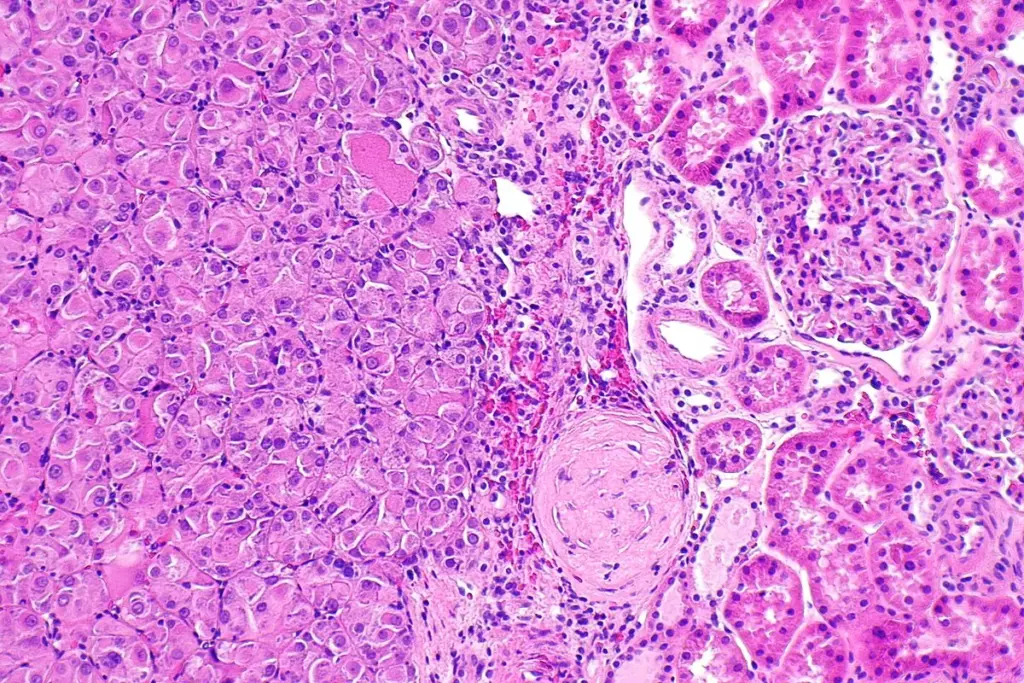

Accurate diagnosis and staging are pivotal for determining the most effective treatment plan. The process typically combines physical examination, imaging, laboratory tests, and tissue biopsy.

Staging follows the FIGO (International Federation of Gynecology and Obstetrics) system, ranging from Stage I (confined to ovaries) to Stage IV (distant metastasis). The table below summarizes each stage and its clinical implications.

Liv Hospital’s state‑of‑the‑art diagnostic suite, combined with expert radiologists and pathologists, ensures precise staging, which directly influences therapeutic decisions and prognostic counseling.